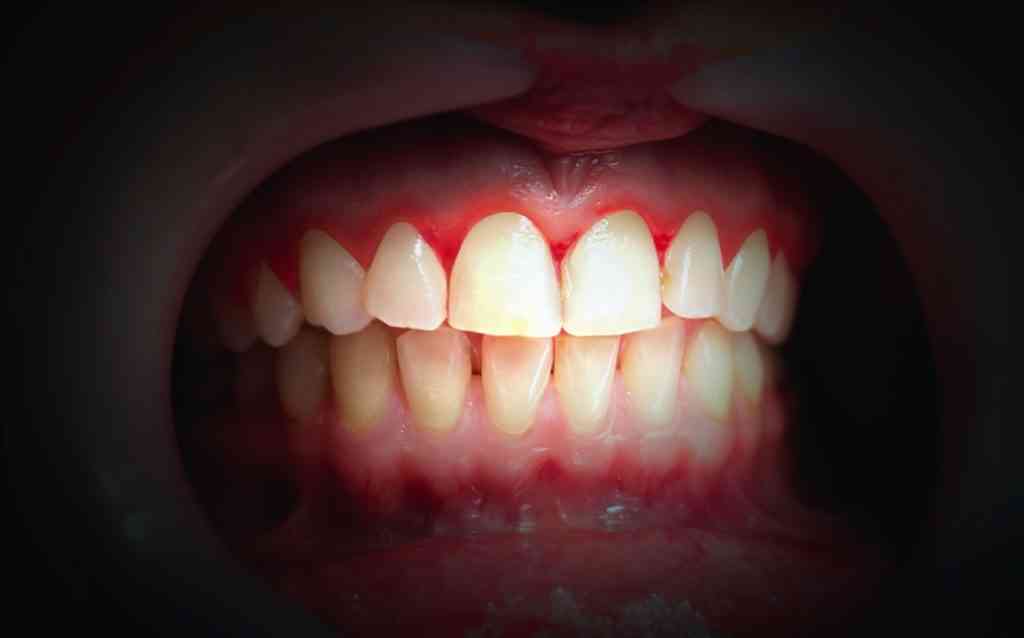

Bleeding gums when you brush or floss is often an early symptom of gingivitis, which can lead to advanced stages of gum disease. Fortunately, this symptom doesn’t mean it’s too late to turn the health of your gums around. There are two components to bleeding gums treatment – quality oral care at home and professional treatment at a dental office.

Many people are diagnosed with gingivitis during a routine office visit. The condition starts out very mild, so it isn’t uncommon for people to be unaware they have it prior to diagnosis. The dental hygienist often notices bleeding, swelling and irritation while cleaning the teeth. During the professional cleaning, plaque and tarter are removed from under the gumline and from the surface of the teeth.

Bleeding gums are a sign that you need to step up your dental hygiene routine at home. Consistent and proper brushing and flossing will go a long way in improving the health of your gums.